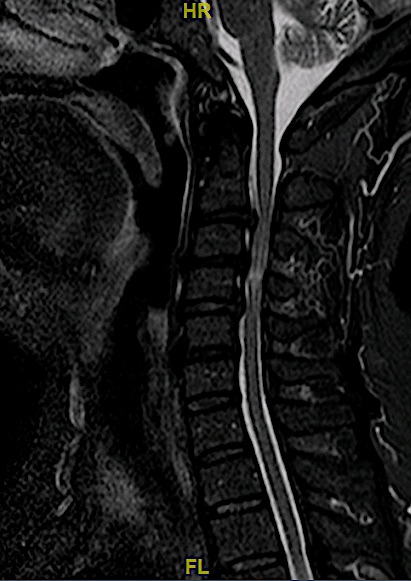

Paciente con clínica de mielopatía que presenta esta RM cervical con una estenosis de canal en segmentos tan inusuales.